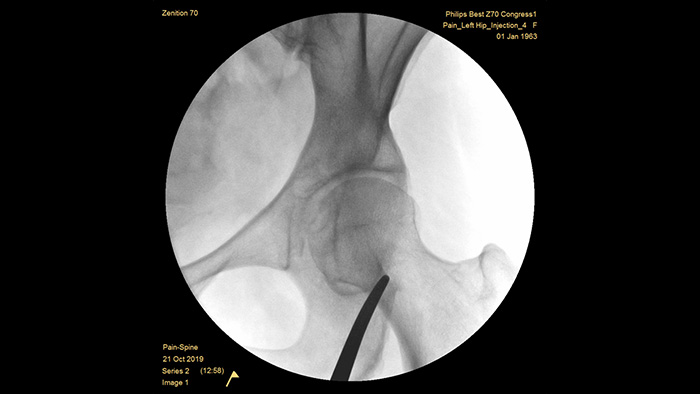

With our fourth generation Flat Detector systems, you gain exceptional image clarity of dense and complex anatomy. The compact form provides ample space and positioning ease for treating chronic pain in the joints. Our Position Memory2 increases first-time-right positioning to reduce scout images3 for efficient workflow in pain management cases. The Zenition 70 is available in two detector sizes: the FD 26 cm x 26 cm offers broad anatomical coverage, while the FD 21 cm x 21 cm provides ample space to work around patients.

Unique pre-configured pain management examination setting allows the users to easily set up the system during the interventional procedures for pain management.

MetalSmart automatically excludes metal artifacts caused by metal implants to provide higher image quality and efficient dose control for pain procedures and patients with metal implants, compared to systems without metal exclusion. BodySmart promotes first-time-right imaging and dose efficiency by automatically adapting the measuring field to the area of interest.